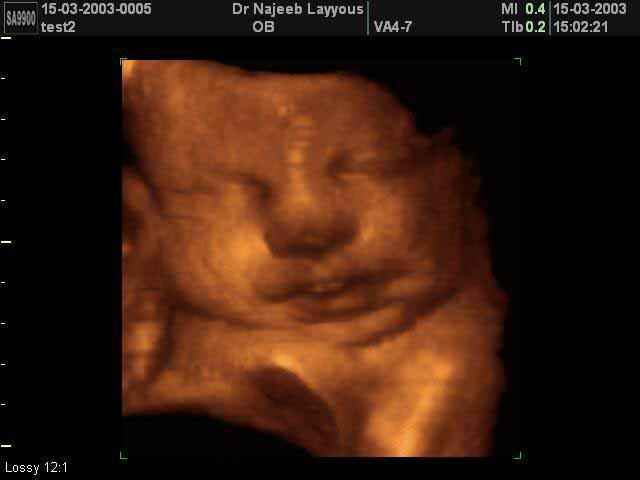

- صور لوجه الجنين في داخل الرحم

صور لوجه الجنين بجهاز الالتراساوند ثلاثي الأبعاد | الدكتور نجيب ليوس